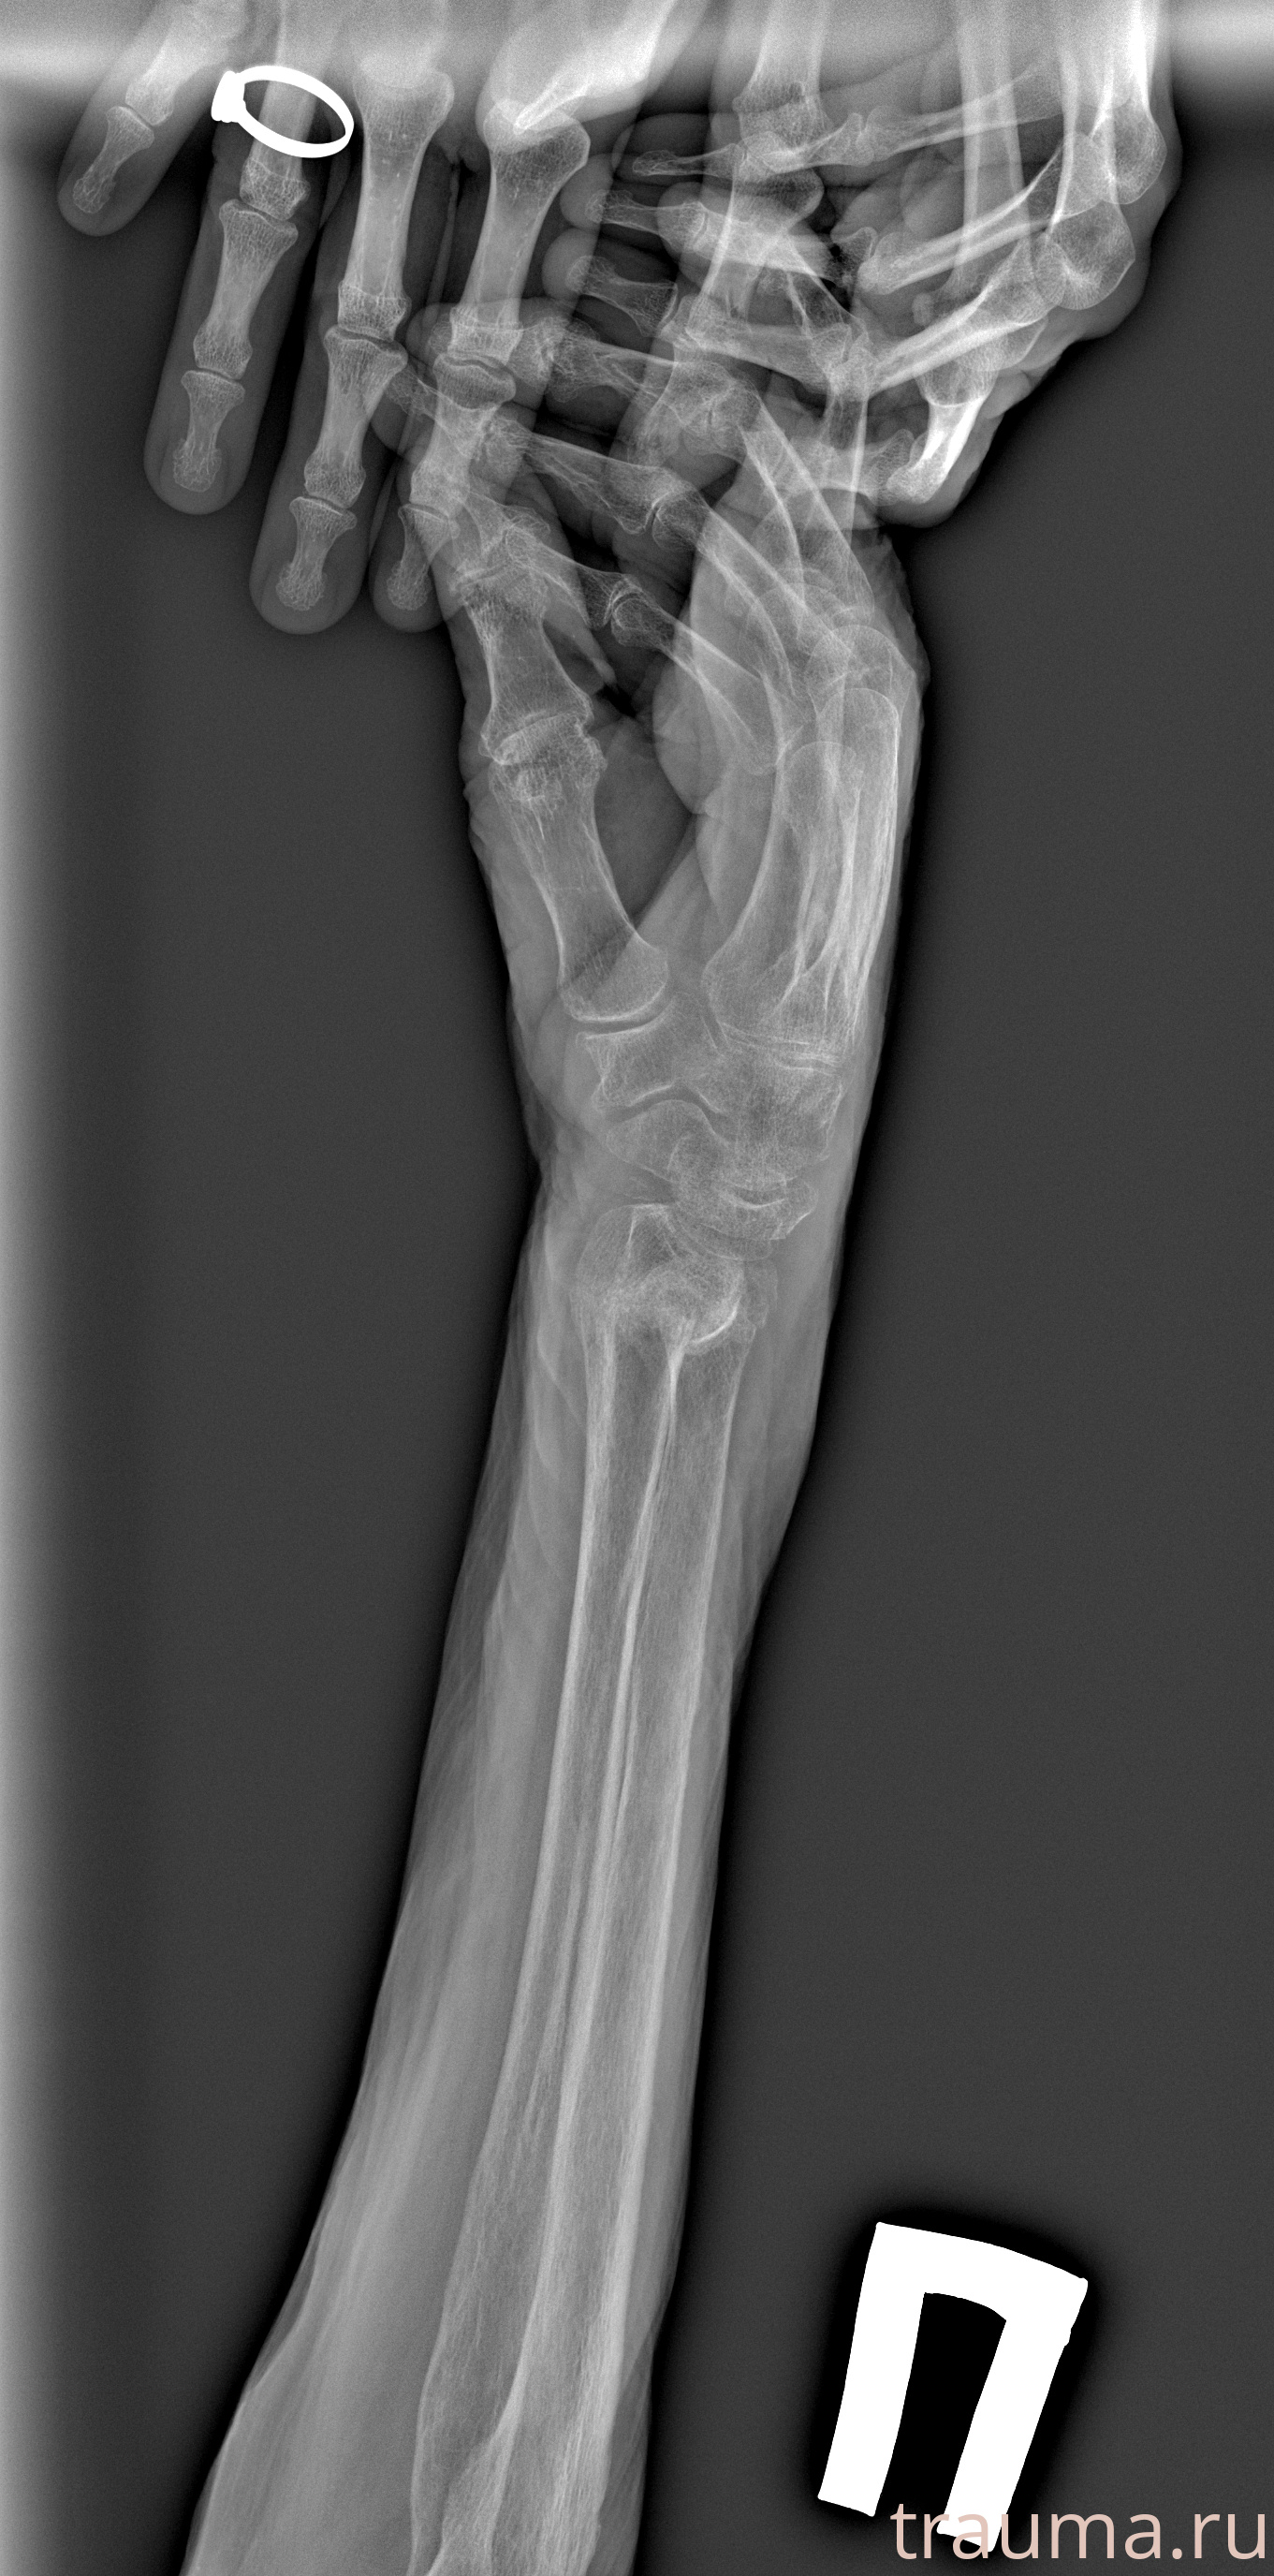

Перелом 3-5 ребер слева